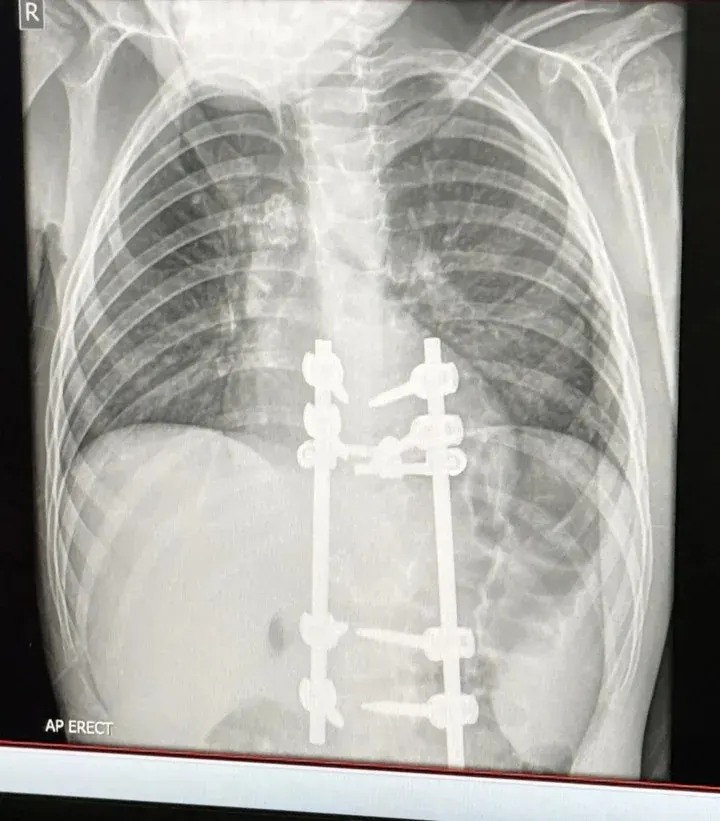

จากการตรวจเพิ่มเติมยืนยันว่า "เอลเลียตป่วยเป็นวัณโรคกระดูกสันหลัง ซึ่งเป็นวัณโรคนอกปอดชนิดรุนแรง โดยเชื้อวัณโรคไม่เพียงส่งผลต่อระบบทางเดินหายใจเท่านั้น แต่ยังลุกลามไปทำลายระบบกระดูก ก่อให้เกิดอาการทางระบบประสาทและการเคลื่อนไหวด้วย!!" และ "หลังการประเมินอย่างรอบคอบ แพทย์ได้ตัดสินใจผ่าตัดให้กับ "เอลเลียต" เพื่อคลายการกดทับของไขสันหลัง และ เสริมความมั่นคงให้กับโครงสร้างกระดูกสันหลัง"

การผ่าตัดครั้งแรกประสบความสำเร็จ "เอลเลียต" สามารถกลับมาเดินได้อีกครั้ง แต่ยังไม่ได้รับอนุญาตให้วิ่งหรือทำกิจกรรมหนัก นอกจากนี้เขายังต้องเข้ารับการผ่าตัดครั้งที่ 2 ภายใน 6 เดือนข้างหน้า หากรอยโรควัณโรคบนกระดูกสันหลังยังไม่ลดลง"